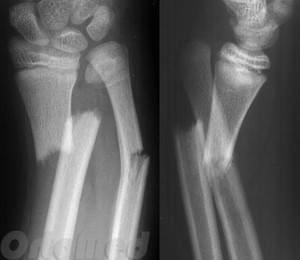

Перелом диафиза лучевой и локтевой кости

Повреждение средней части предплечья возникает вследствие нарушения целостности тела локтевой, лучевой кости или обеих сразу. На первый план выступают боль, припухлость, кровоизлияния в месте повреждения. Резко ограничивается пронация и супинация руки (вращательные движения предплечьем внутрь и наружу). Определить наличие повреждения не всегда удается, так как кости в средней части расположены под слоем мышц. При переломе со смещением может наблюдаться укорочение конечности.

Диафизарный перелом локтевой кости

Механизм повреждения – прямой удар по предплечью. При обследовании пациента с переломом локтевой кости выявляется отек, деформация, резкие боли при прощупывании, осевой нагрузке и сдавлении предплечья с боков. Движения ограничены. При переломе локтевой кости без смещения травматолог фиксирует согнутое предплечье на 4-6 недели. Лонгетой обязательно захватывается два соседних сустава – лучезапястный и локтевой. При переломе локтевой кости со смещением предварительно выполняют репозицию.